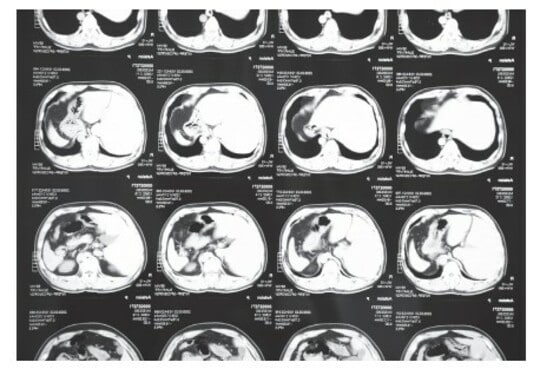

そして1マスごとのX線の透過度合いに合わせてマスに色をつけていけば、下にあるような画像を得られます。

つまりCT画像とは、コンピューターによって画像として再構成されたX線の透過度合いのデータです。直接的に写真を撮影しているわけではないのです。